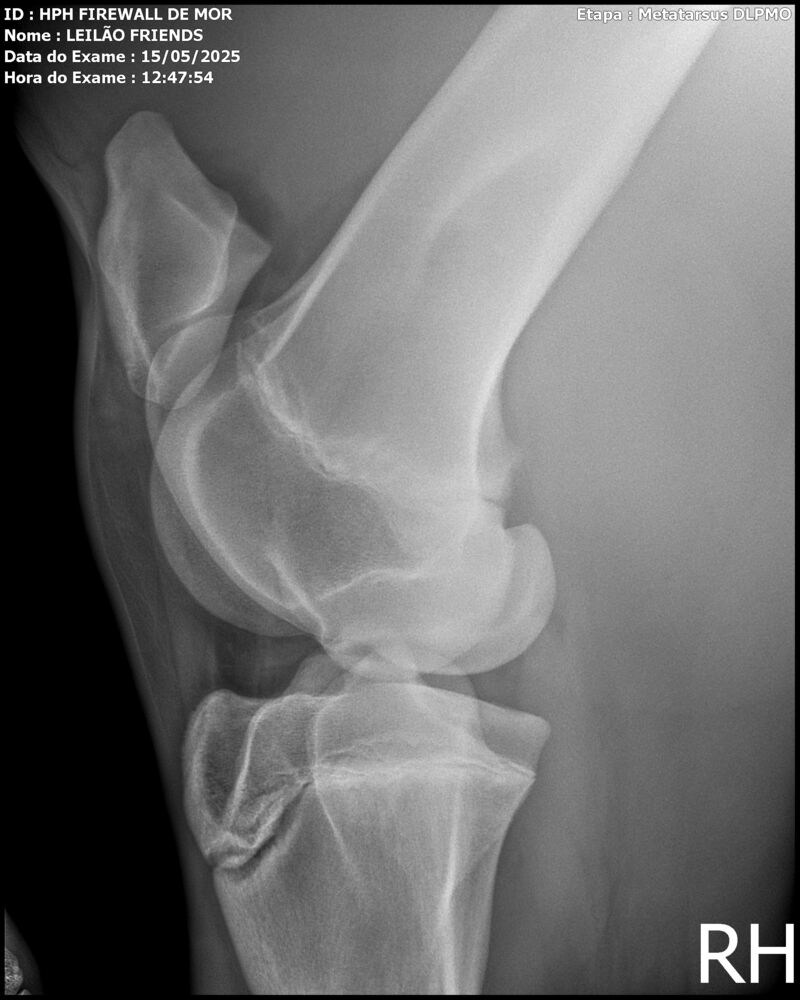

Sexo: MACHO

Nascimento: 13/04/2023

Pelagem: TORDILHA

Altura aproximada: 1,61m

Previsão de altura: 1,66m

Vendedor: HARAS HPH / TRV

Localidade: SÃO PAULO/SP

Garanhão tordilho, apesar de jovem, mostra muito poder e uma plástica de salto incrível. Firewall é sempre muito positivo, busca o salto e os supera com muita agilidade e leveza.